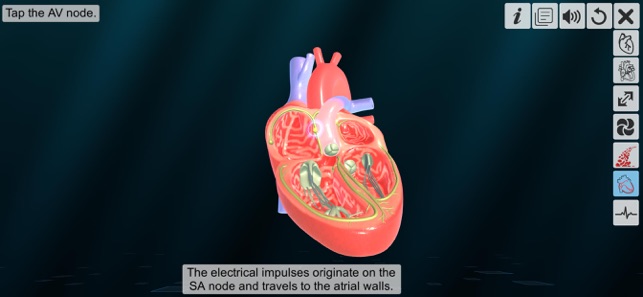

6. Node of heart

‘Heart - An incredible pump’ app explains the external and internal structure of human heart through the simulation 3D model to improve the comprehension of the topic. The user can interact with the 3D model by tapping the model and getting acquainted with the particular part of the human heart. Tapping the model displays the name of the part and also the simulation module is appropriately supported with in depth information about each external and internal structure part.